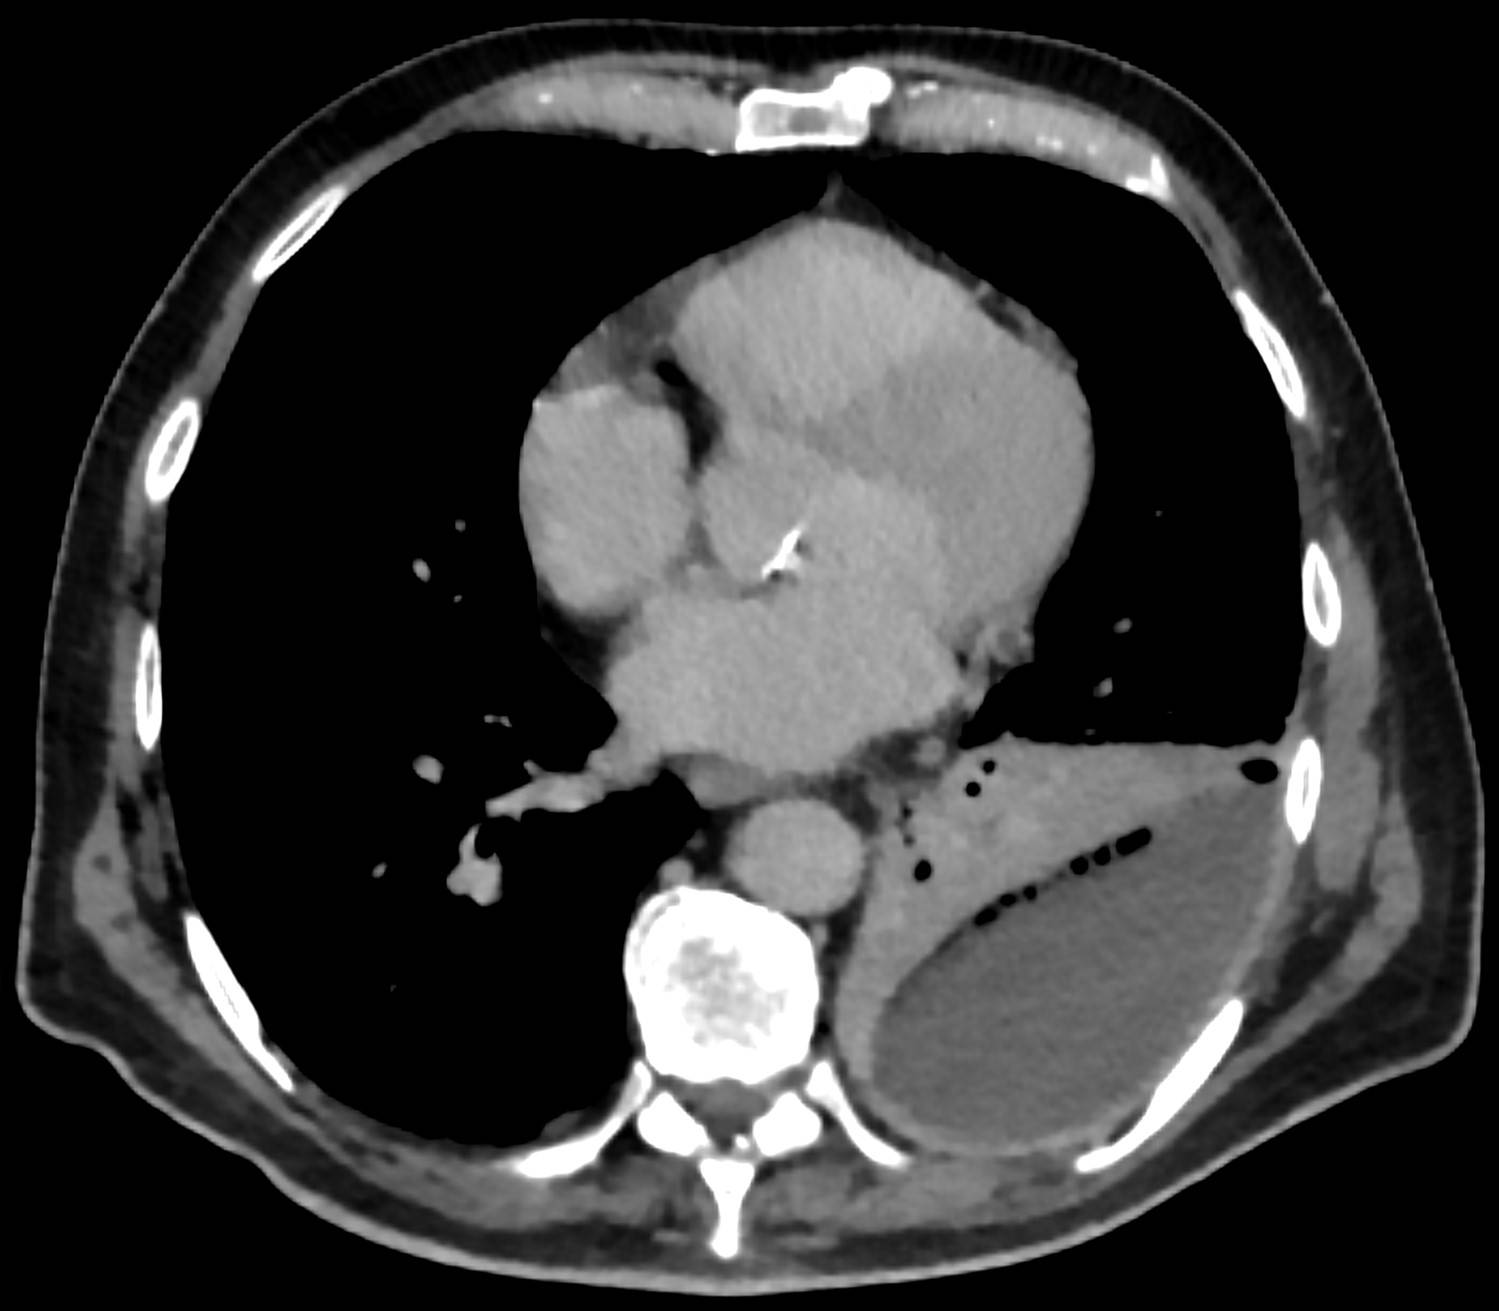

3) CT: CXR과 동일 / 농흉(empyema)와의 감별에 도움

* 농흉(empyema): Pleural space에 농이 찬 상황 (참고: ‘흉막 삼출’)